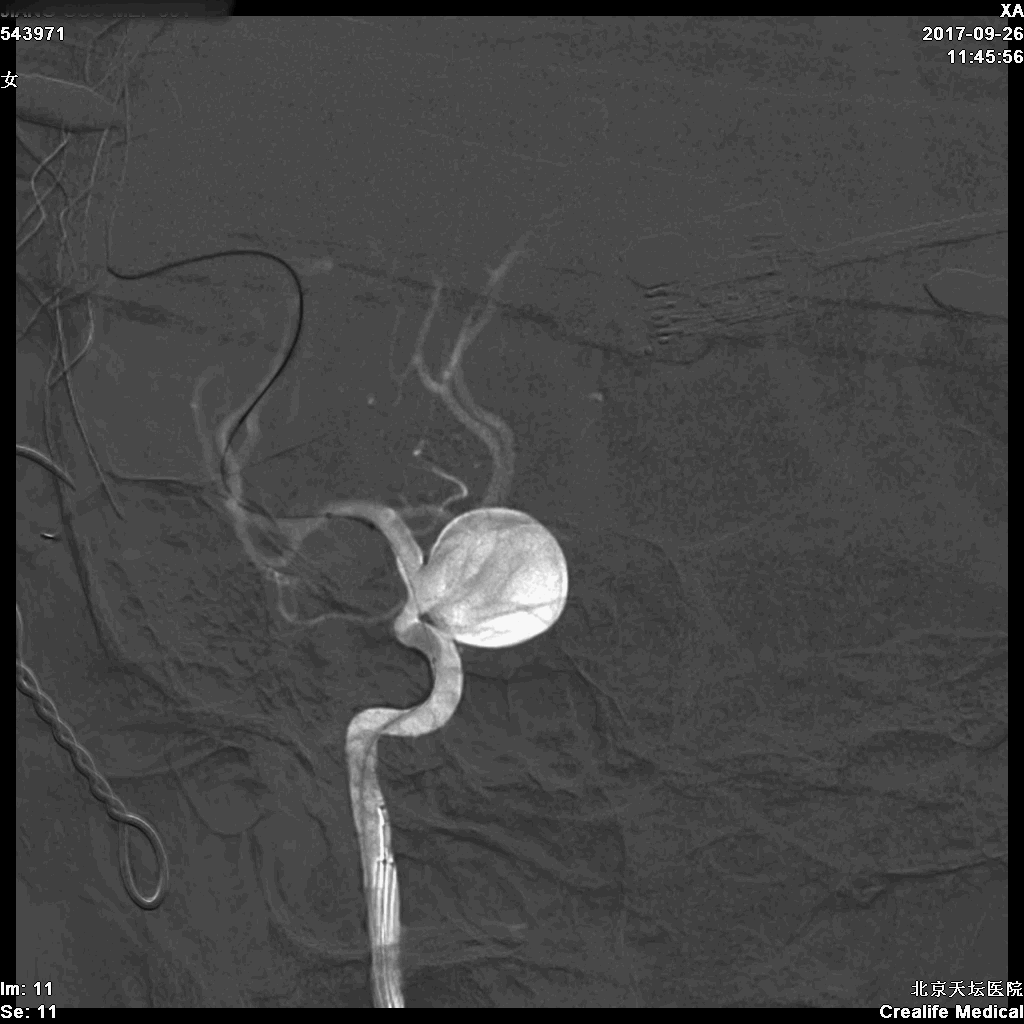

球囊瘤跨瘤颈阻断

开颅后RICA正位DSA